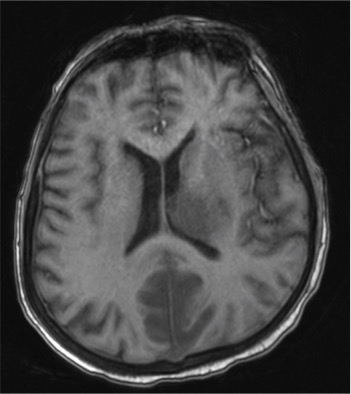

A middle-aged man presented with acute lymphoblastic leukemia (initial white cell count of 150,000 per cubic millimetre of blood – mostly blasts). After completing a course of hyper-CVAD, he developed persistent febrile neutropenia that was unresponsive to antibiotics. On the 6th day of fever, CT thorax was performed which was normal. On the 8th day of fever, he suddenly became drowsy and an MRI brain was performed. Sample images are shown below.

He was brought down to the intensive care unit (ICU) in view of his drowsiness and the brain lesions, and a skin lesion appeared over his face the following day.